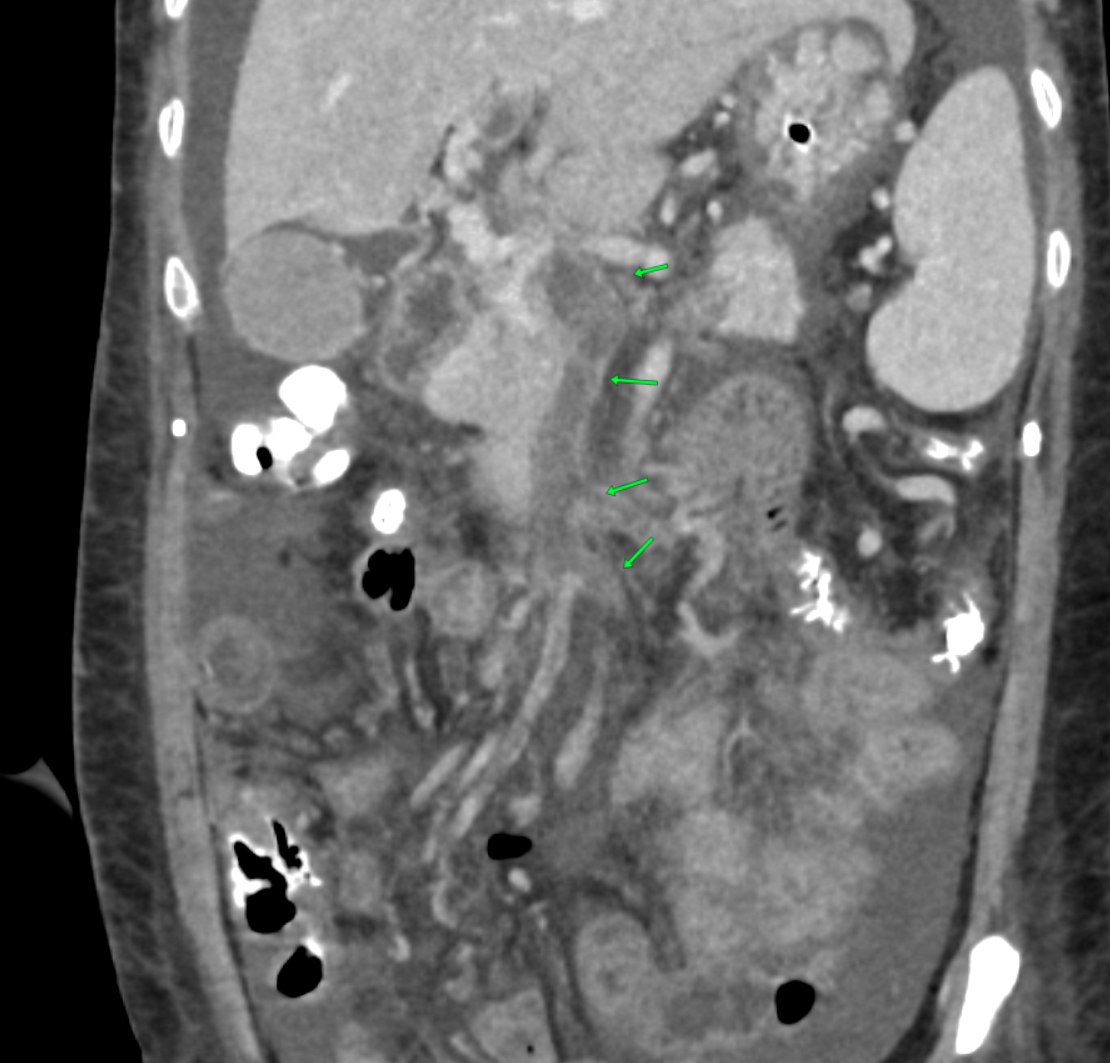

Abdominal CT scan showing the extent of the venous thrombosis, with the green arrows pointing towards the filling defect corresponding to the thrombus along the superior mesenteric vein